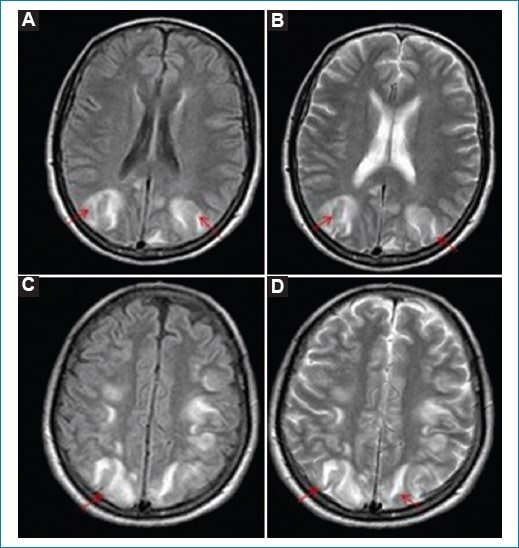

• Hallazgos atípicos: es casi tan habitual como la clásica. Hay afectación de los lóbulos frontales, el tronco, el cerebelo y los ganglios basales. La mayoría de los casos remiten por completo. Las lesiones irreversibles (edema citotóxico) ocurren en el 15% de los casos y se caracterizan por restricción en difusión (Fig. 2)4.

Figura 2. SEPR. Cortes axiales de RM. Se identifica hiperintensidad en difusión (A), que se corresponde con hiperintensidad cortico-subcortical parieto-occipital bilateral (flechas) en la secuencia FLAIR (B).